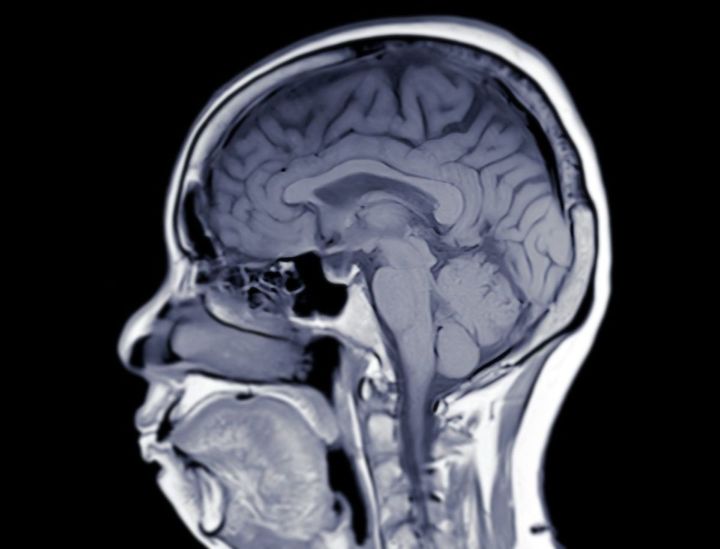

頭部のMRI画像

※写真はイメージです

その数日後、「脳幹梗塞」が起こっていることが判明。搬送された病院主治医から、